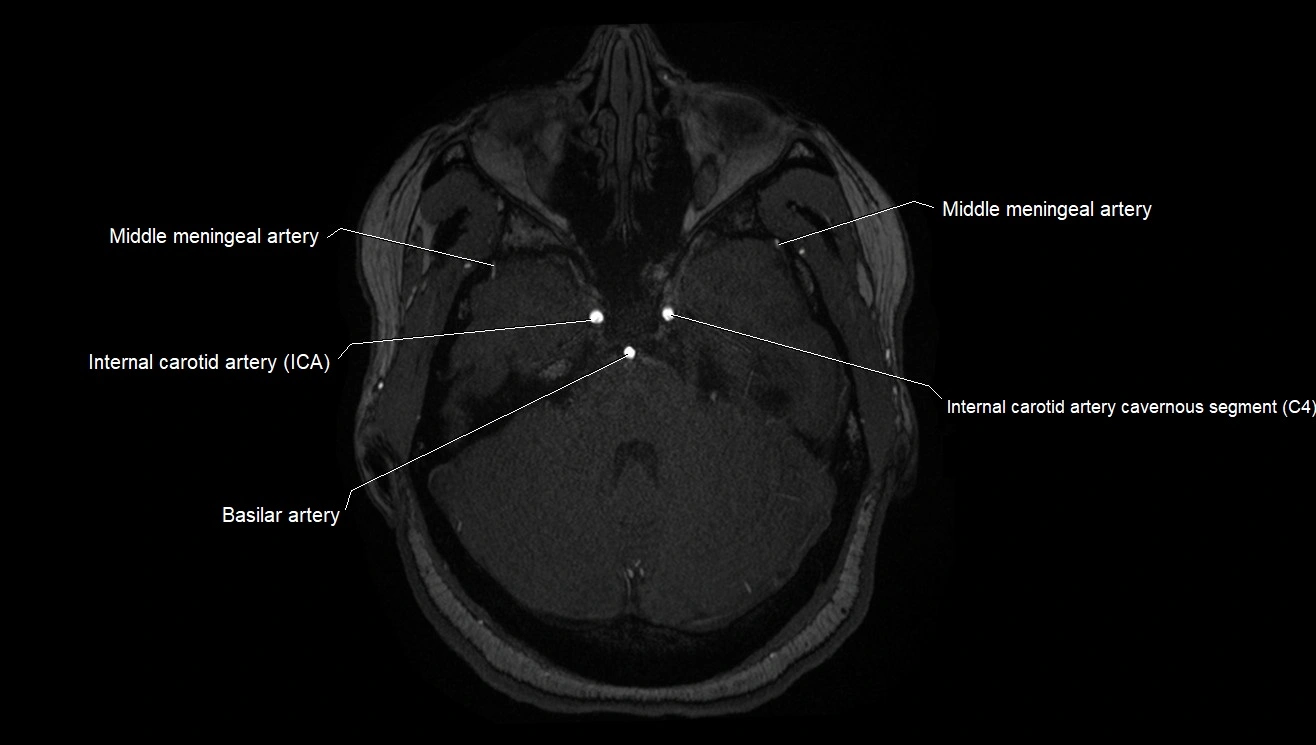

MRI Appearance

T1-weighted images:

• Vessel appears as a flow void (dark lumen) near the optic tract and temporal horn

• Surrounding parenchyma intermediate signal

T2-weighted images:

• Vessel lumen shows dark flow void

• Ischemic infarcts in its territory (internal capsule, thalamus) appear hyperintense

MRA (Magnetic Resonance Angiography):

• Flow-related enhancement makes the AChA appear as a bright, linear vascular signal against suppressed background

• High sensitivity for origin and proximal course; distal branches may be too small to resolve

• Detects stenosis, occlusion, aneurysm, AVM feeders